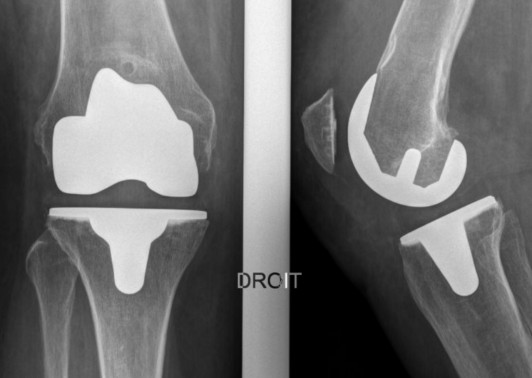

La prothèse de genou est constituée d’implants permettant le remplacement de l’articulation usée.

Elle comporte un carter fémoral, une embase tibiale, tout deux en alliage de Chrome-Cobalt et un plateau en polyéthylène (PE). Lorsque la rotule est usée, elle est resurfacée par un implant en PE.

Les implants fémoraux et tibiaux peuvent être impactés en « press-fit » pour une tenue d’emblée ou bien cimentés. Les implants impactés sont revêtus d’HAP (hydroxyapatite) ou d’un spray Titane permettant une pousse osseuse au contact de la prothèse.